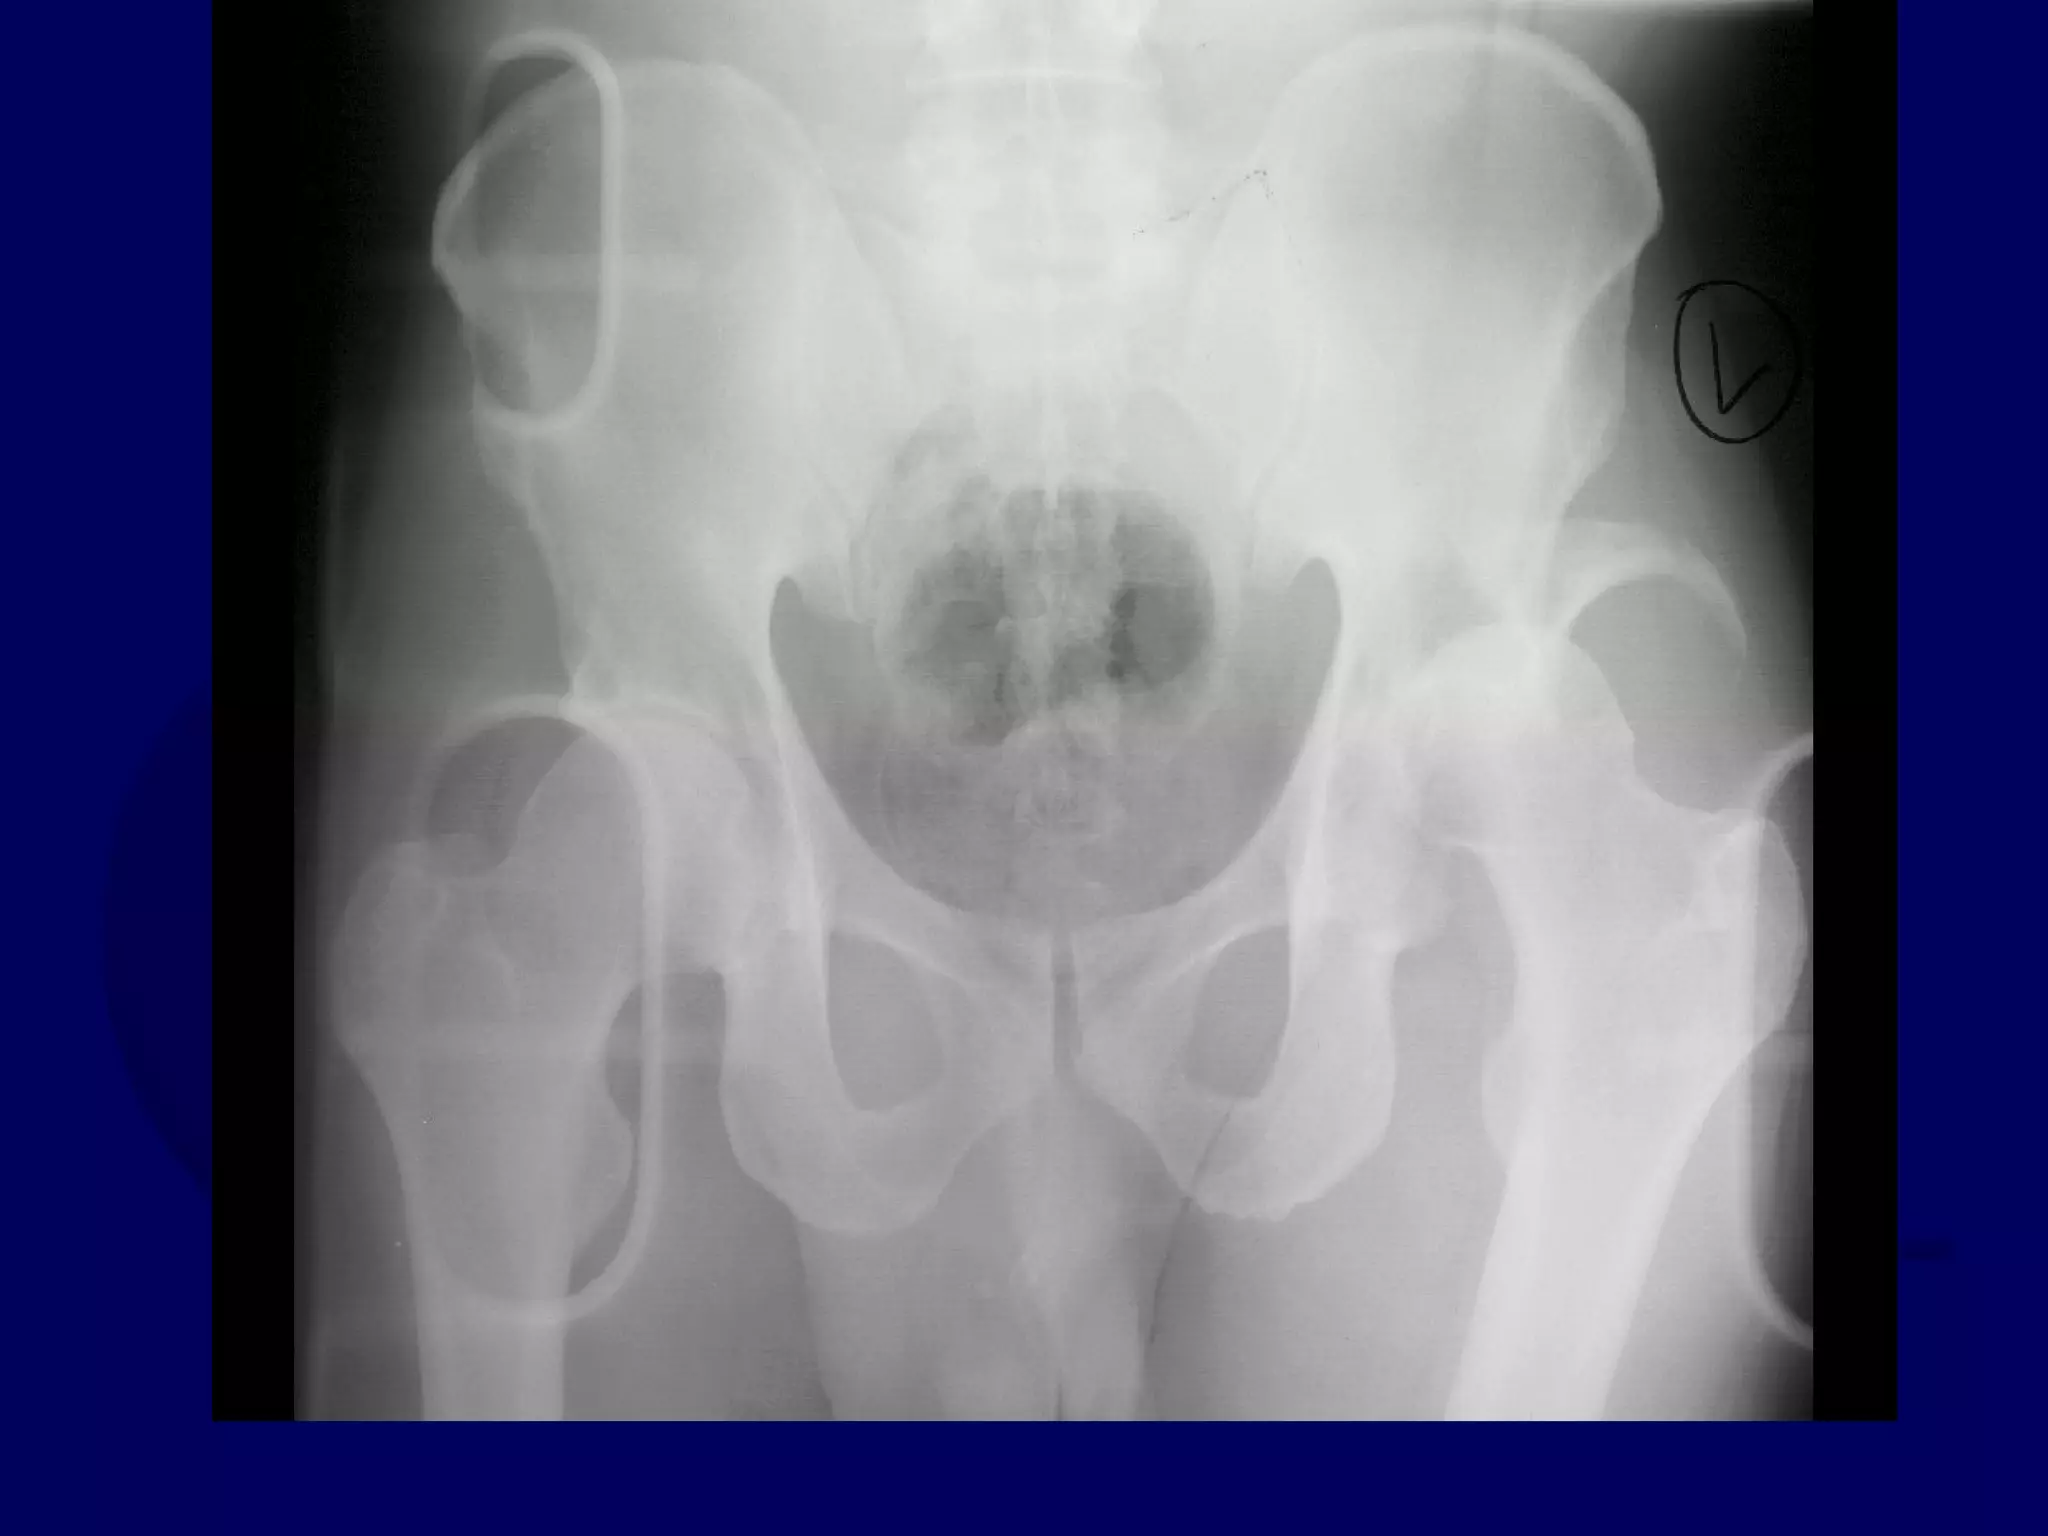

Both Column

Acetabular Fracture

18 Y.O. Female

Isolated Injury

R.C. 00.03.09

SPUR

SIGN